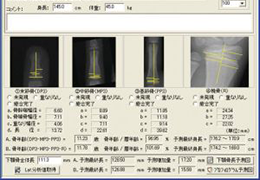

ANYTHINK 经导管主动脉瓣膜置换术分析系统